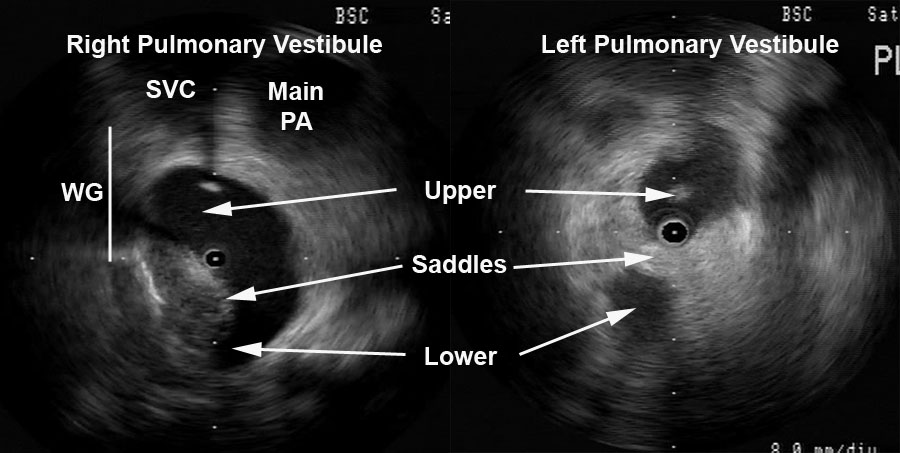

Detailed anatomy of the pulmonary veins can also aid in catheter positioning and stability as well as monitor for procedural complications (discussed later). Figure 3 provides views of the left and right pulmonary vestibules. The left upper (LUPV) and lower pulmonary veins (LLPV) are visualized as are the saddles. The right intervenous saddle is not as clearly differentiated as the left in this particular example to give the reader a better overall view of the structures surrounding the right pulmonary vestibule such as SVC, main PA, and Waterston’s groove (WG). Waterston’s groove is a fat-filled depression formed as the left and right atria fold into one another; Waterston’s groove is often dissected by surgeons to expose the left atrium. Radial ICE can be carefully placed within each individual pulmonary veins to guide catheter ablation as previously described. [1,2,3]

Figure 3  Radial ICE Anatomy of Left and Right Pulmonary Vestibules. The right pulmonary vestibule is shown with the early portions of the upper and lower pulmonary veins. Superior to the right pulmonary veins one can see the main pulmonary artery and superior vena cava. The approximate location of Waterston’s groove is depicted by the solid line.  A more distal view of the left pulmonary vestibule (compared to Figure 2) clearly differentiates the upper and lower PV’s as well as the intervenous saddle.